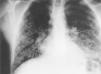

Un varón de 32años de edad, con antecedentes de fumador de unos 20cigarrillos al día y adicción a la cocaína,acude al servicio de urgencias por disnea intensa, con tos yexpectoración hemoptoica. Una semana antes habíainiciado fiebre elevada, astenia y artralgias, apareciendo a las48-72 h unas lesiones cutáneas diseminadas, decaracterísticas vesiculopustulosas en diferente estadioevolutivo (fig. 1). En la radiografía de tórax seobservó un patrón nodular intersticial bilateral(fig. 2).

El pacienteingresó en la unidad de cuidados intensivos porinsuficiencia respiratoria grave y evolucionó favorablementecon la administración de aciclovir intravenoso yoxigenoterapia, sin llegar a precisar apoyo ventilatoriomecánico. Diagnóstico: neumonía por varicelazoster.